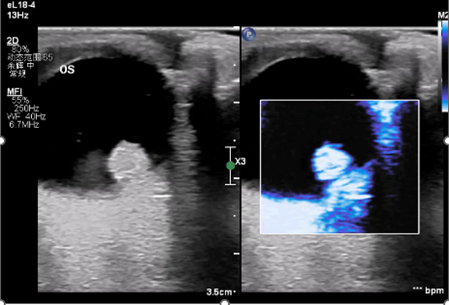

超声检查不仅能够直观的观察眼部病变形态结构,更是目前唯一能够反应眼部血管血流动力学的影像学检查方法。然而由于眼部血管分布密集表浅,普通超声检查的分辨力和敏感性无法满足精准诊断的临床需求。超微血流成像技术是一种新型的可以检测出高分辨率和最小伪影的小血管血流的检测方法,可以用于检测组织中缓慢和微弱的血流解剖。但对于视网膜动静脉栓塞,高血压、糖尿病等视网膜病变,肿瘤病变良恶性鉴别等仍存在不足。近年来随着超声造影技术的迅速发展,超声造影技术对微小血管和低流速、低流量血流信号具有更高的检出率,并且能更优质的显示组织血流的灌注特点。超声造影其独特的显像特点将在眼部占位,眼部血管性病变中取得更大的发展。将超声造影联合超微血流成像技术应用于眼底病变的观察可能为眼科疾病的诊断和鉴别诊断提供一种创新的融合显像检查方法。